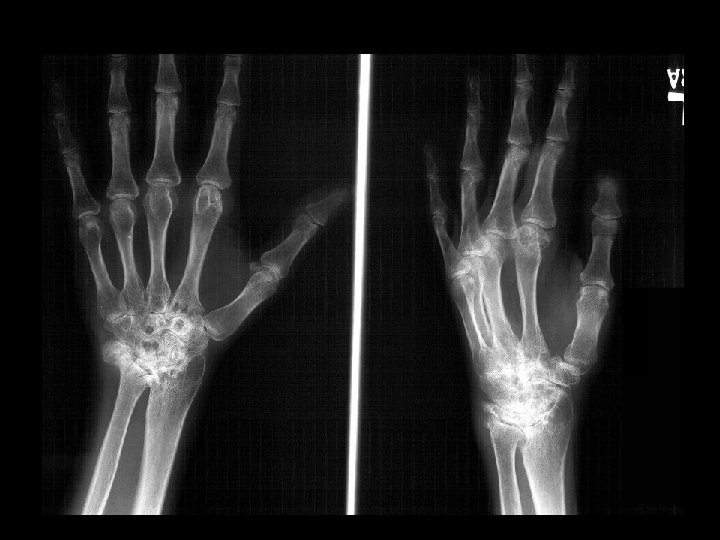

Endstage: SLAC Wrist